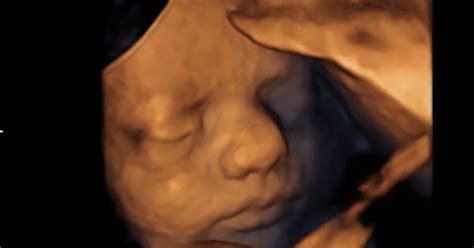

Oči vašega dojenčka so zdaj sposobne razlikovati med svetlobo in temo, veke pa se lahko odpirajo in zapirajo. Na jeziku se razvijajo prve okušalne brbončice, kar omogoča dojenčku, da okuša okuse v plodovnici, ki jo pije. Ta razvoj vida in okusa je tesno povezan z razvojem možganov, katerih površina postaja vse bolj nagubana, kar kaže na intenzivno rast možganskega tkiva. Proporci otrokovega telesa so vse bolj podobni tistim ob rojstvu; glava zdaj raste počasneje, da jo lahko preostanek telesa dohiteva. Ker otrok še nima dovolj podkožne maščobe, je koža še vedno nagubana, vendar se bo to s kopičenjem maščobnih celic spremenilo do rojstva.

Otrok ima vzpostavljen ritem budnosti in spanja, ki pa se pogosto ne ujema z vašim. Pogosto bo aktiven ravno takrat, ko si vi želite počivati ali zaspati. Ta aktivnost je del priprave telesa na porod, saj so hormoni, ki igrajo ključno vlogo pri porodu, aktivni tudi v času vašega počitka, otrok pa se na njih odziva. Kljub temu, da otrok še nima podkožne maščobe, se prične kopičiti teža, namenjena pripravi na življenje zunaj maternice. V 27. tednu nosečnosti otrok običajno meri dobrih 36 centimetrov in tehta okoli 0,86 kilograma, kar pomeni, da se nahaja v sedmem mesecu nosečnosti.